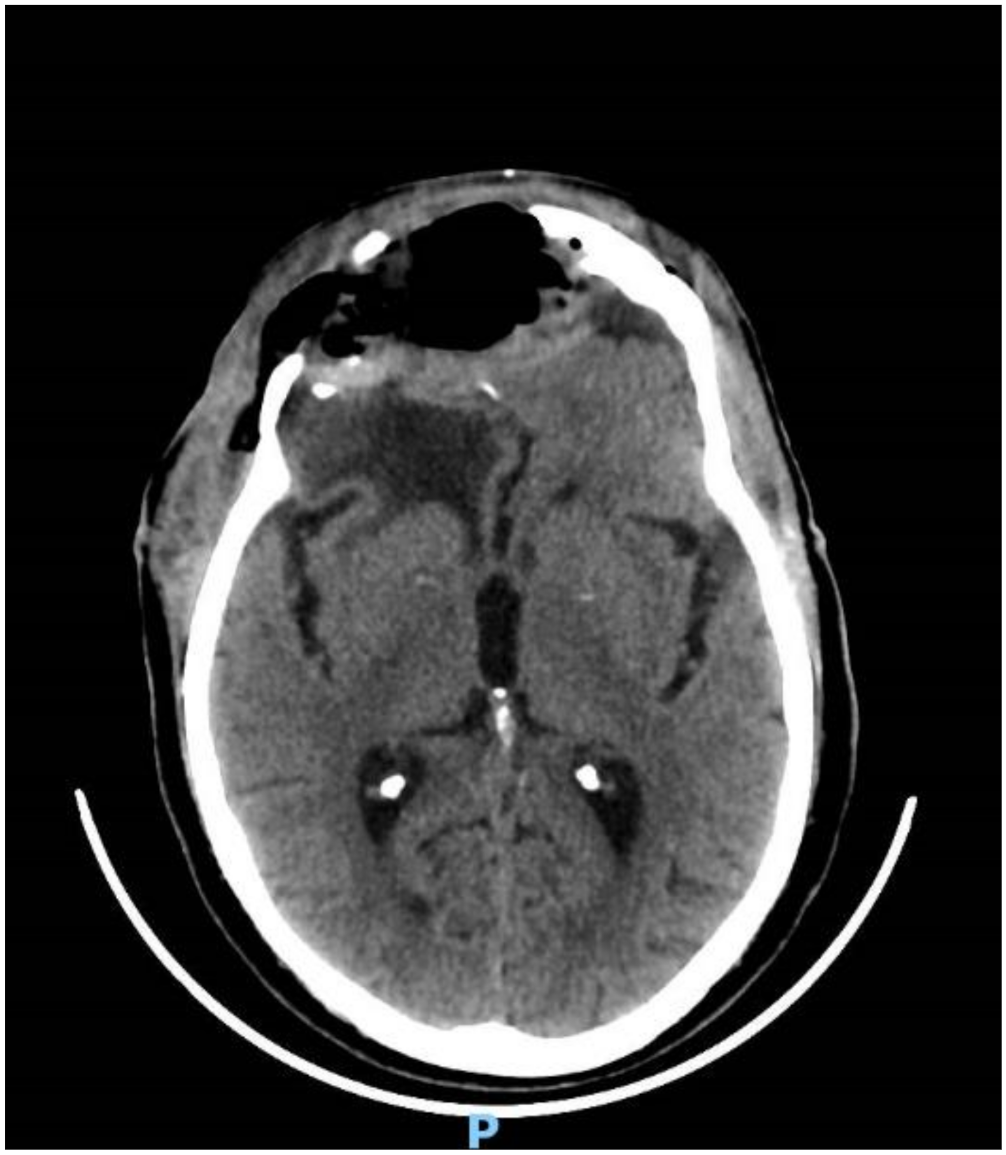

His clinical history started in 2012 with headaches, visual disturbances and behavior’s changes. MRI documented a spheno-ethmoidal lesion with a homogeneous contrast enhancement and with involvement of right anterior skull base (Figure 1). The patient underwent right subfrontal craniotomy with tumor resection. A post-operative MRI showed the apparently complete excision of lesion (Figure 2). Histopathology confirmed the radiological suspicion of meningioma (WHO I). The patient was discharged without complications.

Figure 1.

Pre-operative brain MRI showing the anterior cranial fossa meningioma with perilesional oedema.